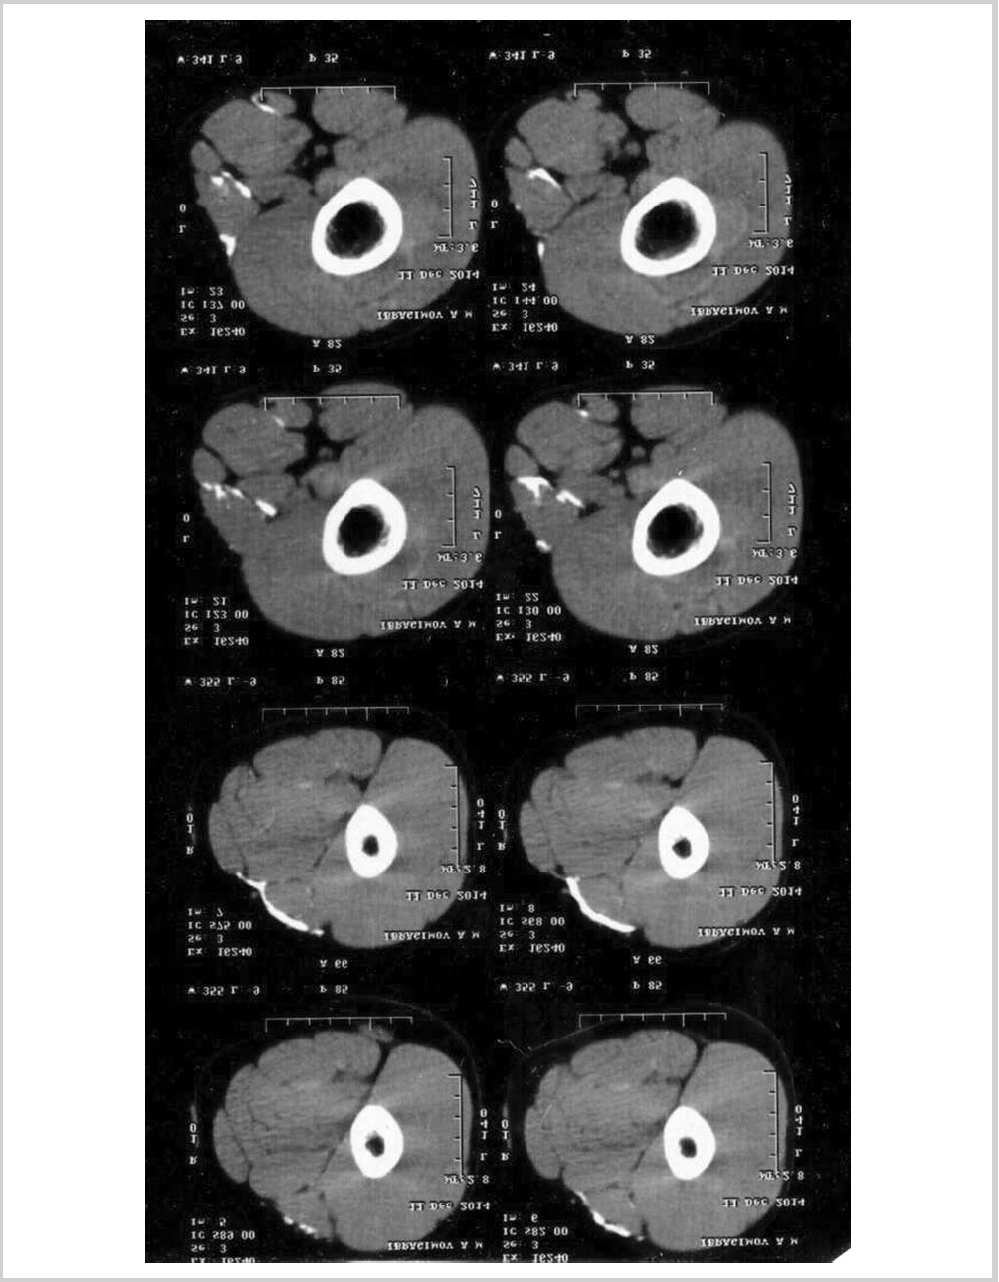

11. Рис. 12. Синдром Фара — кальцинаты в ткани головного мозга.

Subject

Type Исследовательские инструменты

View (88KB)